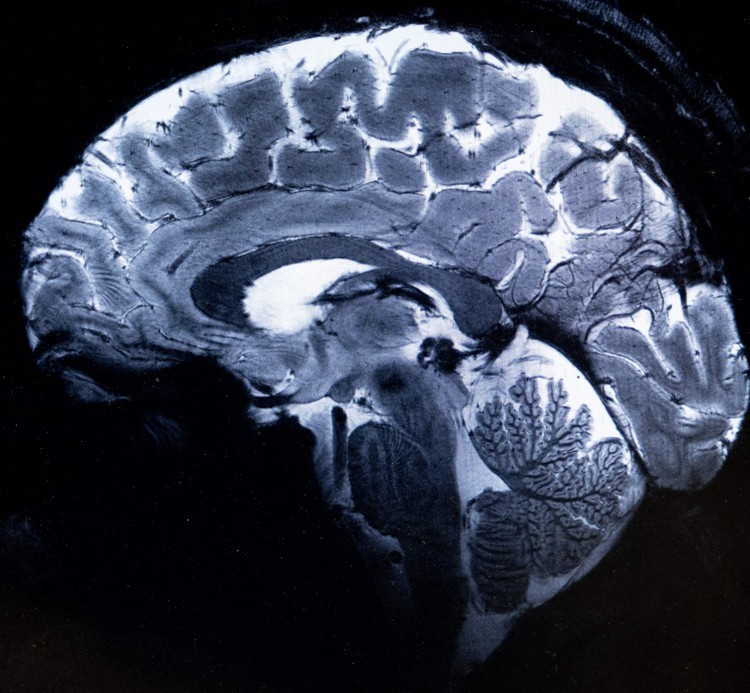

Enquanto os participantes jogavam, os pesquisadores estimulavam seus cérebros com estimulação transcraniana por corrente alternada sobre os lobos frontal, a parte do cérebro responsável pela tomada de decisões, e o lobo parietal do cérebro, vital para o paladar, a audição, a visão, o tato e o olfato. A estimulação foi configurada para fazer com que as células cerebrais nessas áreas disparassem juntas em padrões repetitivos, treinando-as para ritmos de oscilação gama ou alfa.

Os autores observam que não registraram diretamente a atividade cerebral durante os testes e, portanto, estudos futuros devem combinar a estimulação cerebral com eletroencefalografia para demonstrar o efeito direto da estimulação na atividade neural. Mas os resultados sugerem que as escolhas altruístas podem ter como base a atividade sincronizada dos lobos frontal e parietal do cérebro.